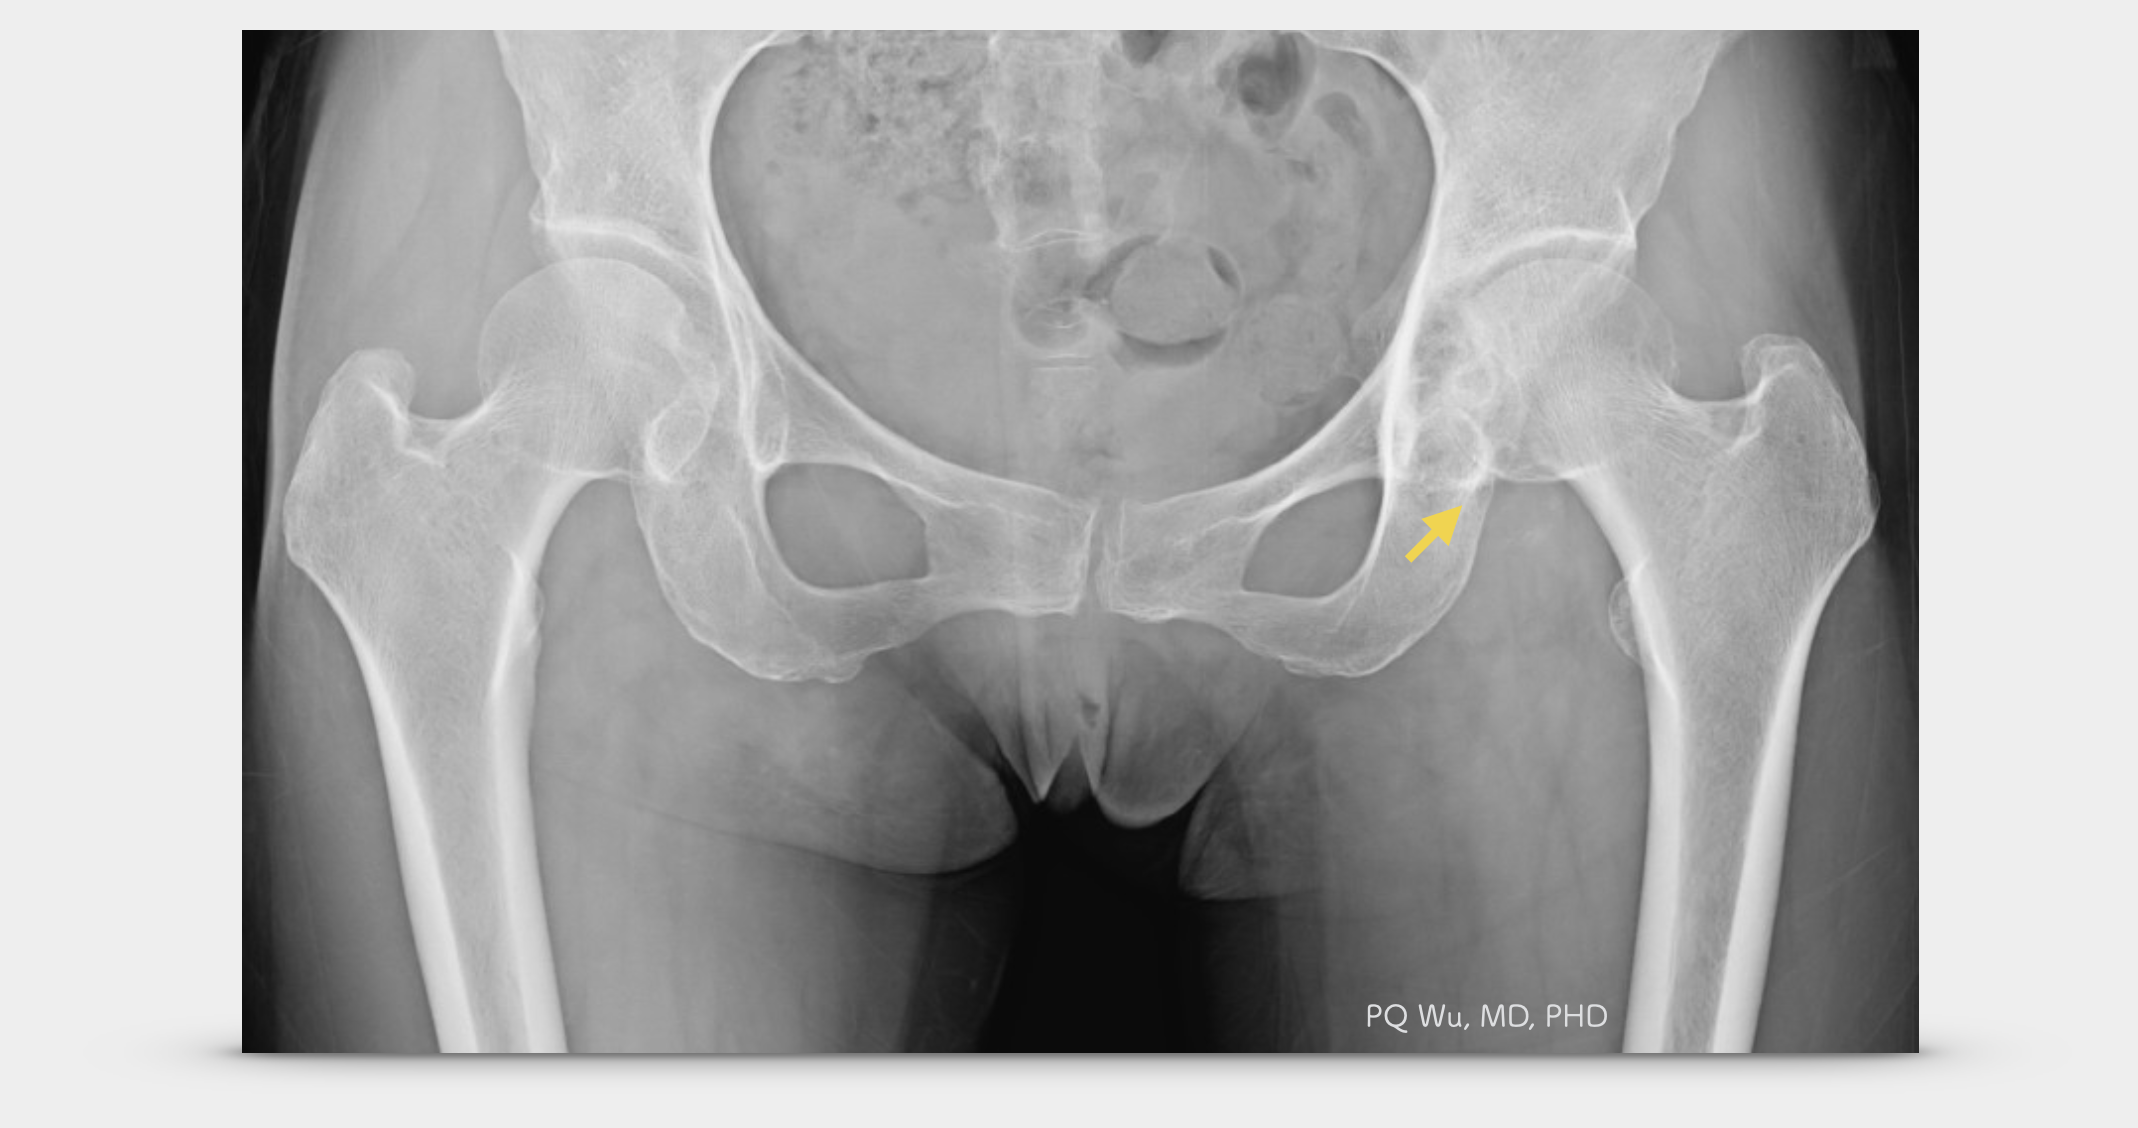

在X光的影像之中,發生在膝關節之腱鞘巨細胞瘤可以見到軟組織腫脹的現象,較少見到骨骼組織的破壞。但若是發生在髖關節附近的腱鞘巨細胞瘤,則常會見到合併骨骼結構的破壞,而有時不易與缺血性股骨頭壞死做區分。

58歲女性,左髖腱鞘巨細胞瘤(X光)

58歲女性,左髖腱鞘巨細胞瘤(MRI)